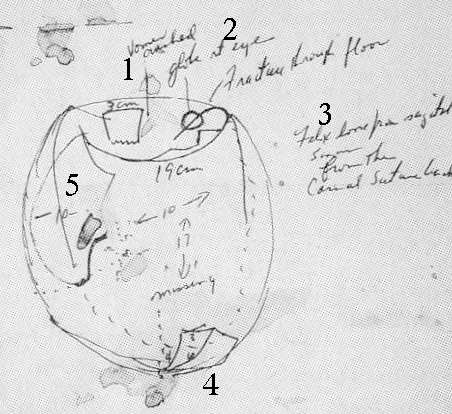

That's what "photo experts" like Robert Groden (in The Killing of a President, page 81) and Harrison Livingstone (in High Treason II) do. Wanting to show the back of Kennedy's head blown out — and thus push the notion of a Grassy Knoll shooter — they use a close-up autopsy photo of the inside of Kennedy's skull after the brain was removed. By rotating the photo ninety degrees clockwise, they can make it appear that the photo shows a large defect in the back of Kennedy's head. In actuality, Kennedy was photographed from the front, and the photo shows the top if his head blasted out, as shown in this drawing by Dr.

Robert Artwohl. Finally, a large and properly-oriented copy of the head photo.

Die Skizze im face sheet S. 2, bei missing", 17 cm

mit besserer Qualität

http://www.history-matters.com/archive/jfk/arrb/master_med_set/pdf/md1.pdfHow did a 17-cm skull defect on the night of the autopsy shrink in the autopsy report? Boswell told the HSCA, [360] the ARRB, and one of the authors (Aguilar, in a recorded call)[361] that it all had to do with the aforementioned beveled bone fragment. The skull defect started out at 17-cm., but after the fragment was replaced into the backside of JFK’s skull, the remaining gap then measured “only” 13-cm., the dimension cited in the autopsy report.